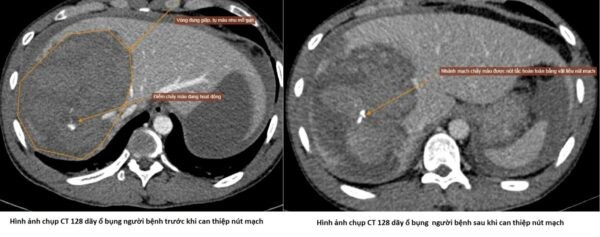

Hình ảnh chụp CT 128 dãy ổ bụng người bệnh trước và sau can thiệp nút mạch cầm máu - Ảnh BVCC

Người bệnh được chẩn đoán: Đa chấn thương do tai nạn giao thông: Vỡ gan độ IV, chấn thương ngực kín, gãy xương đốt bàn ngón V bàn tay phải. Đặc biệt, chụp cắt lớp vi tính đa dãy (CT 128 dãy) cho thấy nhu mô gan phải có vùng đụng giập tụ máu KT ~ 87x108mm, trong có hình ảnh ổ thoát thuốc hoạt động, nhiều dịch máu ổ bụng, nguy cơ diễn tiến nguy kịch nếu không được can thiệp kịp thời.

Sau hội chẩn liên chuyên khoa, các bác sĩ đã thống nhất chỉ định can thiệp nút mạch cầm máu chấn thương gan – một kỹ thuật cao, ít xâm lấn, giúp kiểm soát chảy máu hiệu quả, hạn chế tối đa nguy cơ phẫu thuật mở. Ca can thiệp diễn ra thuận lợi tại Trung tâm Chẩn đoán hình ảnh và Điện quang can thiệp dưới sự hỗ trợ của hệ thống máy chụp mạch số hóa xóa nền (DSA) hiện đại.

Các bác sĩ đã xác định chính xác vị trí mạch máu tổn thương và tiến hành nút mạch cầm máu thành công, kiểm soát hoàn toàn tình trạng chảy máu trong gan. Ngay sau can thiệp, người bệnh được chuyển về Khoa Cấp cứu để tiếp tục theo dõi và điều trị.